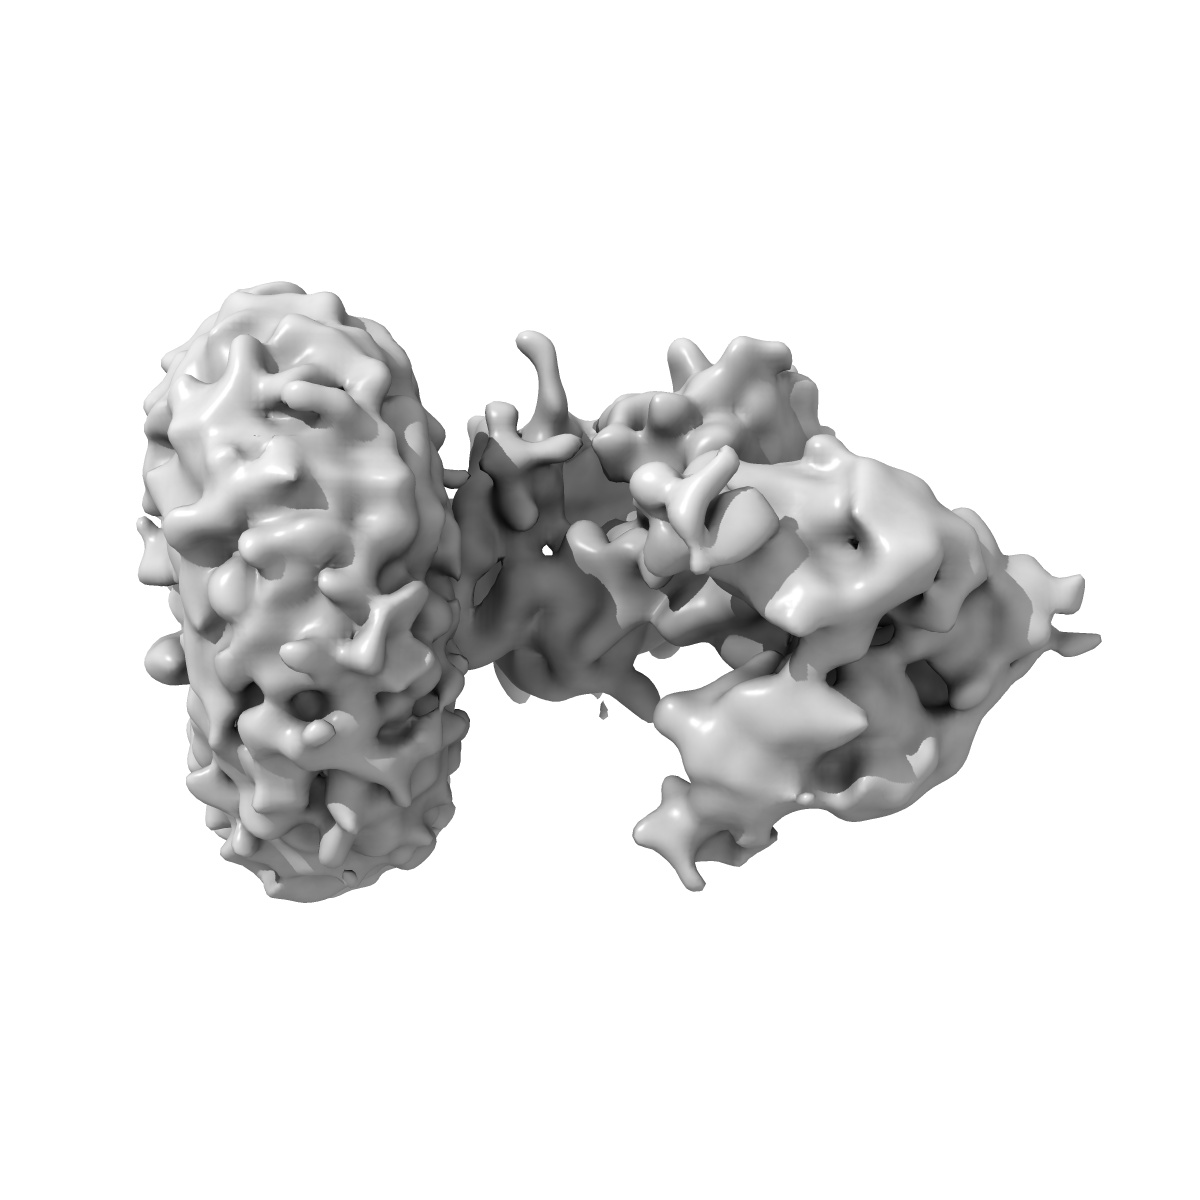

cryo-EM map of the full-length human NPC1 in complex with the cleaved glycoprotein of Ebola virus

Sample: NPC1 in complex with EBOV-GPcl trimer

Structural Insights into the Niemann-Pick C1 (NPC1)-Mediated Cholesterol Transfer and Ebola Infection